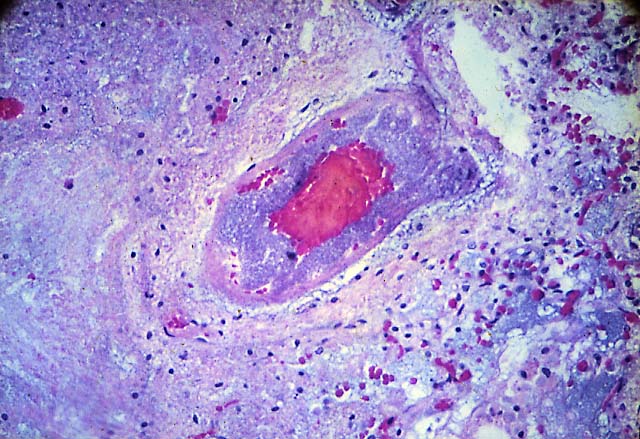

Il cambiamento nel numero e nella tipologia dei geni che si esprimono in ogni fase dello sviluppo porta dapprima alla determinazione del destino differenziativo delle cellule e in momenti successivi alla loro effettiva differenziazione nei diversi tipi cellulari presenti nell'organismo adulto. In alcuni tessuti dell'adulto permangono cellule che non andranno mai incontro al processo di determinazione e differenziamento, mantenendo la capacità di rinnovarsi. Queste cellule sono dette appunto «staminali», cellule in grado di sostituire quelle differenzianti nei tessuti caratterizzati da un alto ricambio cellulare (ad esempio, le cellule del tessuto ematopoietico,le cellule del sangue) o da processi di continua morte cellulare (ad esempio nell'epidermide). Le cellule staminali mantengono capacità proliferativa durante tutta la vita dell'individuo e quando si moltiplicano danno origine a una cellula che rimane di tipo staminale mentre l'altra inizia il processo differenziativo. Si dice così che le cellule staminali si dividono in modo asimmetrico poiché le due cellule figlie hanno destini differenziativi funzionali diversi. Con il procedere dello sviluppo embrionale e fetale, il numero di cellule staminali si riduce e nell'individuo adulto sono presenti solo in alcuni precisi distretti tissutali. Dalle blastocisti si possono isolare le cellule del nodo embrionale e coltivarle fino a ottenerne milioni, le cosiddette cellule embrionali staminali la cui caratteristica principale è l'elevata capacità proliferativa unita alla capacità di differenziarsi in qualsiasi altro tipo cellulare. Da questa descrizione deriva il concetto di cellula staminale:un particolare tipo di cellula che ha la unica capacità di rinnovare se stessa e di dare origine a uno dei più di duecento tipi diversi di cellule specializzate (osso, muscolo, nervi...) presenti nel corpo. In altre parole, la gran parte delle cellule che compongono il corpo, ad esempio le cellule della pelle, sono specializzate per compiere una funzione specifica mentre le cellule staminali rimangono indifferenziate sino al momento in cui ricevono degli stimoli che le portano a svilupparsi in cellule specializzate, differenziate.

Le caratteristiche delle cellule staminali ne permettono un impiego in medicina rigenerativa per terapie cellulari mirate a sostituire le cellule perse nel corso della senescenza o a causa di traumi o patologie. Basti pensare al trapianto di cellule staminali ematopoietiche che, negli ultimi vent'anni, ha rappresentato una valida terapia per la cura di alcuni tumori del sangue e per gravi malattie ematologiche anche non neoplastiche. L'impiego dellecellule staminali somatiche soffre di due grandi limitazioni, l'una numerica (sono molto poche e di difficile reperibilità) e l'altra fisiologica (dopo alcune divisioni cellulari in coltura tendono a perdere le caratteristiche di multipotenzialità). Diversamente, le cellule ES possono essere mantenute in coltura per moltissimi cicli di divisione, addirittura per più di dieci anni, senza perdere la pluripotenzialità ma la loro produzione incontra forti resistenze e limitazioni di natura etica: il problema è l'embrione !